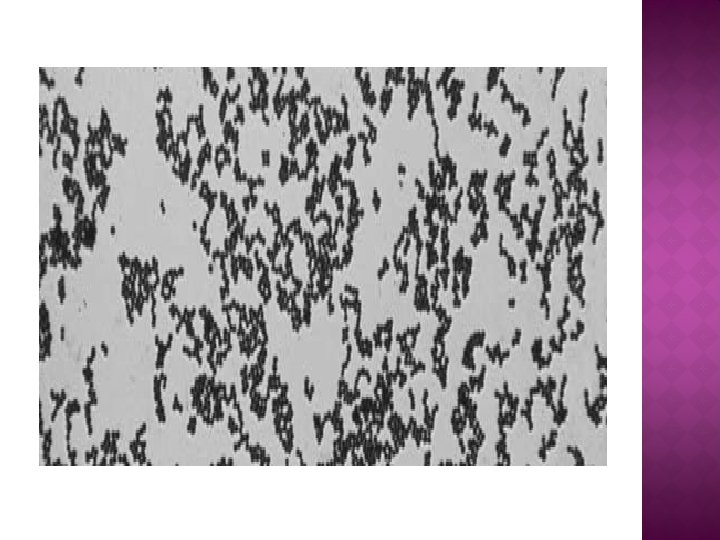

Gram-positive cocci, mostly in pairs and short chains, found in cerebrospinal fluid from a 34 -year-old man with Streptococcus suis meningitis.